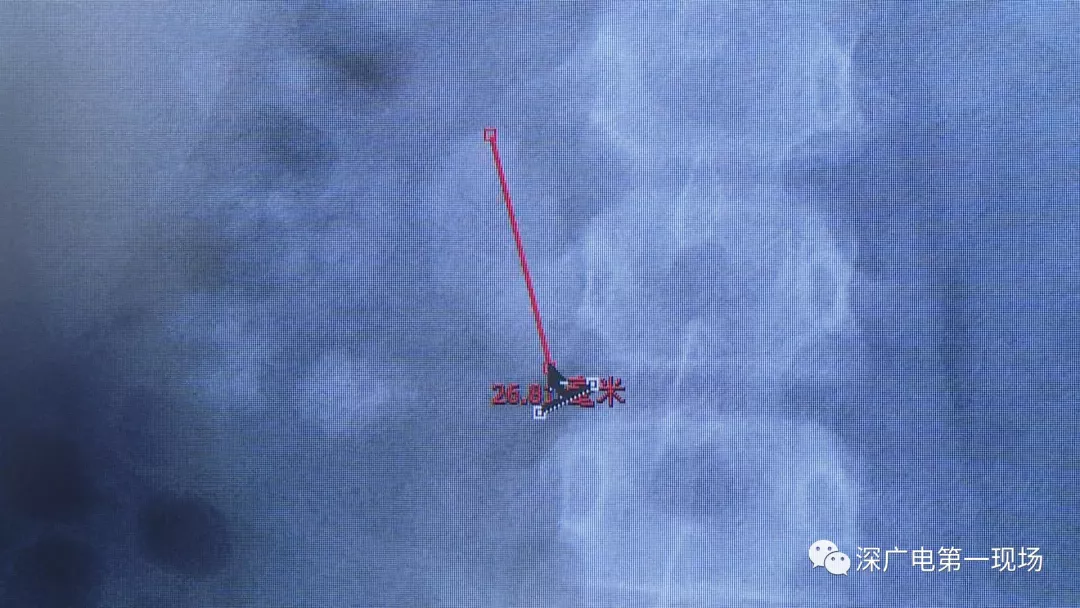

小軒這種情況,其中,最大的結(jié)石長約2.7厘米,寬約1.7厘米,體積堪比鵪鶉蛋,不但造成了尿路堵塞,還導致了右腎中度積水。